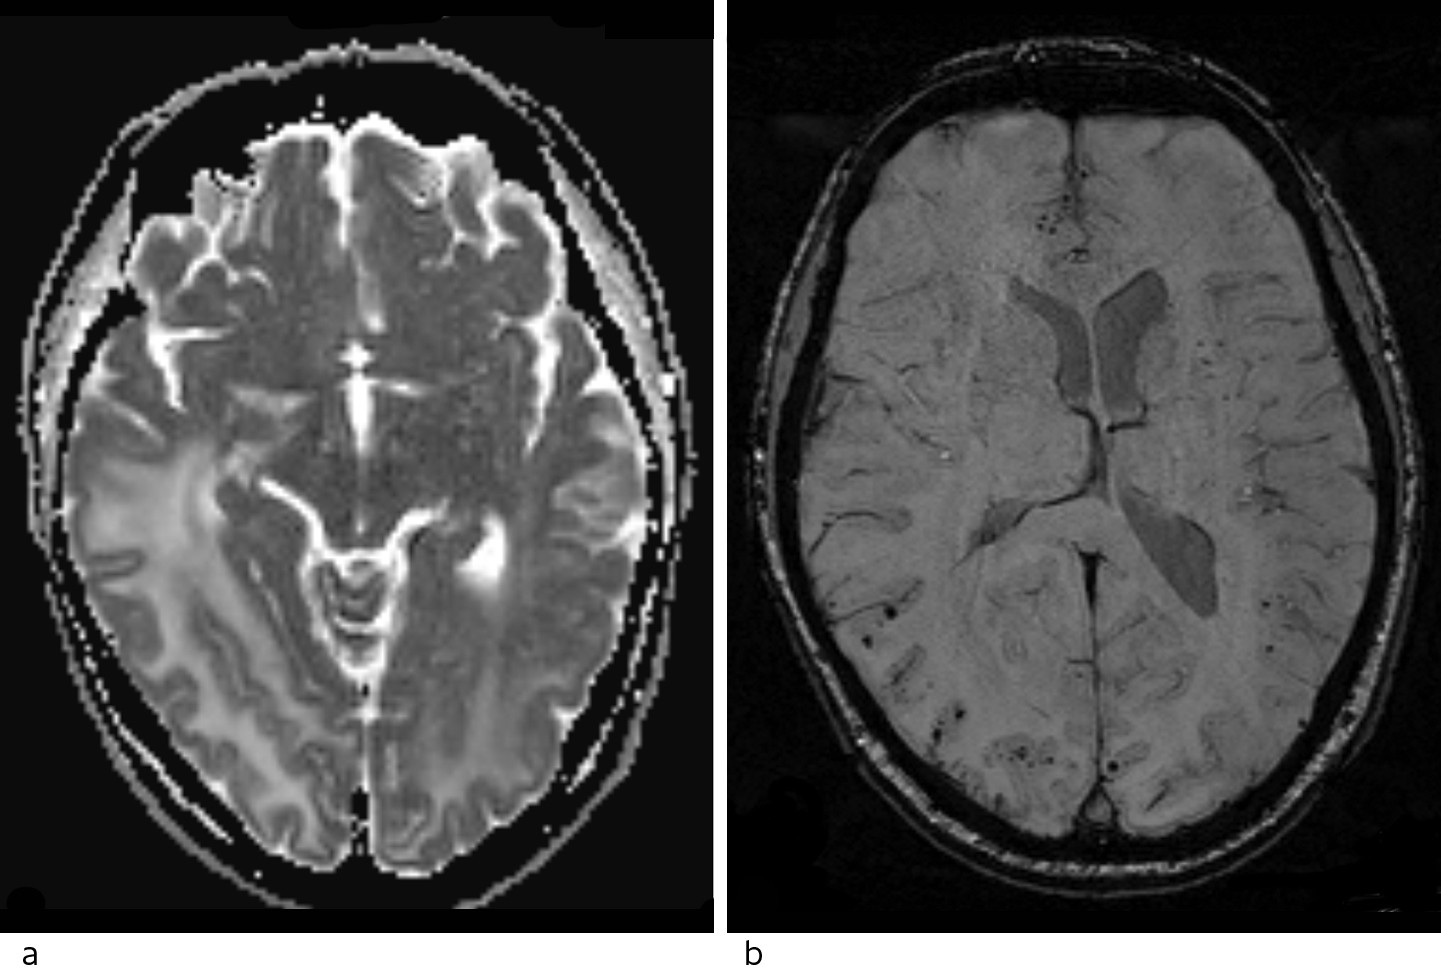

Pasienten ble undersøkt med CT caput uten og med intravenøs kontrast. Det ble sett lavattenuasjon, som ved ødem i hvit substans oksipitalt, mest uttalt på høyre side med masseeffekt og midtlinjeforskyvning mot venstre (fig 1).

MR caput med intravenøs kontrast (fig 2) viste økt signal i hvit substans i høyre temporal- og oksipitalregion samt i mediale venstre oksipitalregion ved T2-vekting og FLAIR-sekvenser. Det var ingen restriksjon på diffusjonsvektet serie (vanlig ved hjerneinfarkt, abscess og i svulster), men økt ADC-verdi (apparent diffusion coefficient). Dette tydet på økt vanninnhold i hjernevevet, best forenlig med et vasogent ødem. Det var ingen patologisk kontrastoppladning eller kontrastladende lesjoner, noe som talte mot metastaser, abscess eller primær hjernesvulst, men man så tallrike punktformige blødninger i cortex i de aktuelle områdene på suceptibilitetsvektet sekvens. MR-spektroskopi viste normal metabolittfordeling, som også talte mot tumor.

Ut fra sykehistorien, sykdomsforløpet og MR-funn med vasogent ødem og multiple kortikale småblødninger i oksipitalregionene, vurderte vi at diagnosen posterior reversibel encefalopati-syndrom var mest sannsynlig, forårsaket av tumorrettet behandling med regorafenib.

Radiologisk er syndromet preget av karakteristiske funn med ødem i hvit substans, oftest i bakre (parieto-oksipitale) deler av hjernen (5). I motsetning til bilaterale bakre infarkter, er oftest calcarine og paramediane deler av oksipitallappen uten ødem. MR spiller en viktig diagnostisk rolle (8), da lesjonene har økt signal på MR-bilder med T2-vekting og FLAIR-kontrast. Vanligvis har disse lesjonene en høy ADC-verdi på diffusjonssekvensen, en indikator på vasogent ødem og dermed reversibilitet og bedre prognose (9, 10). Bruk av suceptibilitetsvektede sekvenser (SWI, en forholdsvis ny metode) har vist at mikroblødninger er vanlig i affiserte områder hos pasienter med posterior reversibel encefalopati-syndrom, hovedsakelig i cortex, men også i hvit substans (8).